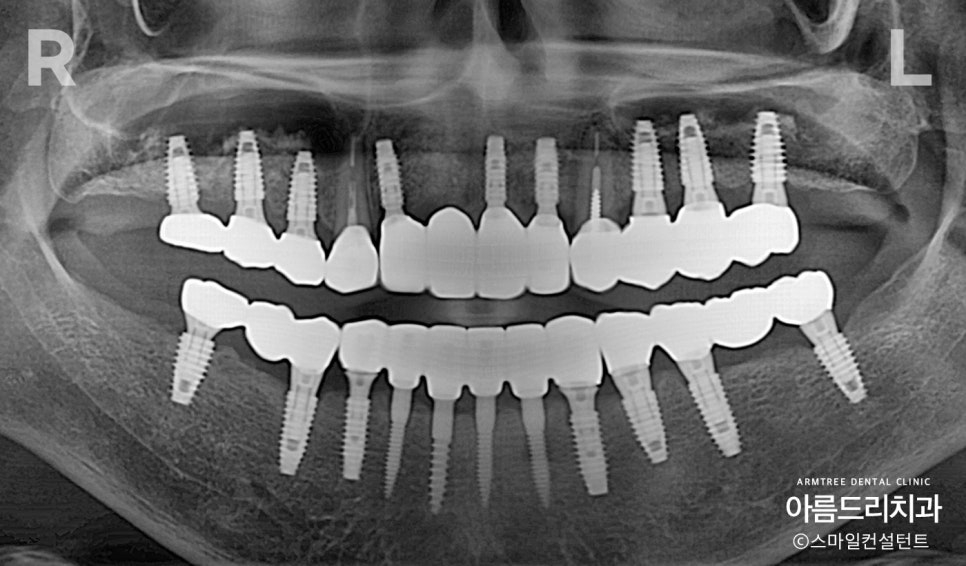

전악임플란트 치료전 사진(상악/하악)

환자분의 전체임플란트 치료 전 사진

(상악/하악)부터 보여드리도록 하겠습니다.

전악임플란트 식립과 머리부분(크라운)까지

모든 치료가 잘 끝난 상태입니다.